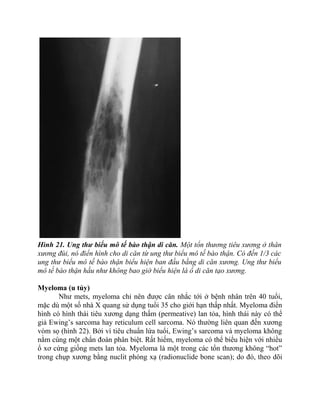

Hình 19. Lymphoma nguyên phát của xương. Tiêu xương dạng thấm

(permeative) được nhìn thấy ở khắp xương cánh tay bệnh nhân 35 tuổi, nó đặc

trưng cho lymphoma nguyên phát của xương.